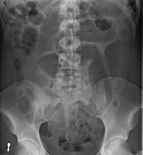

An x-ray of a person with a small bowel volvulus.

Plain X ray of a cecal volvulus